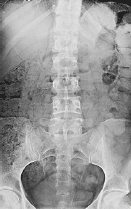

ΠΑΡΑΓΟΝΤΕΣ ΕΜΦΑΝΙΣΗΣ ΤΗΣ ΚΗΛΗΣ

Στους παράγοντες που συντελούν στην εμφάνιση κήλης του μεσοσπονδυλίου διαστήματος είναι η κληρονομική προδιάθεση, η ηλικία, η κακή στάση του σώματος, το υπερβολικό σωματικό βάρος, οι τραυματισμοί, η άρση βάρους, κ.α.

Η πίεση στους δίσκους προκαλεί δυνάμεις εκτονώσεως του πυρήνα που ασκούνται στα τοιχώματα του δίσκου, εάν δε υπερβούν την αντοχή του, τότε μέρος του δίσκου προβάλει στον σπονδυλικό σωλήνα. Αποτέλεσμα είναι η δημιουργία της κήλης, η οποία προκαλεί συμπτώματα όταν πιέζει τις ρίζες των νεύρων.

Η ύπαρξη της κήλης μεσοσπονδυλίου δίσκου επιβεβαιώνεται με Αξονική ή την Μαγνητική Τομογραφία.